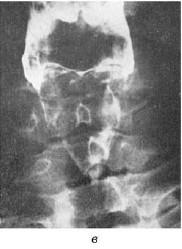

В боковой проекции отчетливо видны надгортанник, щитовидный и перстневидный хрящи, хуже визуализируется область черпаловидных хрящей. Для улучшения обозримости гортани и отдаления задней стенки ее от тел шейных позвонков обследуемому в момент экспозиции предлагают закрыть нос и сильно подуть в него (наподобие опыта Вальсальвы). Раздувание надгортанного пространства и гортаноглотки приводит к более отчетливому проявлению краев надгортанника, области черпаловидных хрящей и желудочков гортани.

Рис. 19.15. Схематическое изображение опознавательных признаков гортани в боковой (а) и прямой (б) проекциях (по Земцову Г. В., 1958). Объяснения в тексте

Рис. 19.17. Рентгенограмма гортани в боковой проекции с использованием рентгеноконтрастного вещества (а) и схематическое изображение ее опознавательных признаков (б); рентгенограмма гортани с напылением в прямой проекции (в) (по Pana I., 1973): 1 – ротоглотка; 2 – гортаноглотка; 3 – надскладочное пространство (rimavestibuli); 4 – подскладочное пространство (cavum inragloticum seu regio infraglotica); 5 – межскладочное пространство (rima glotidis); 6 – трахея; 7 – контуры гортани, визуализированные аэрозольным напылением контрастного вещества;